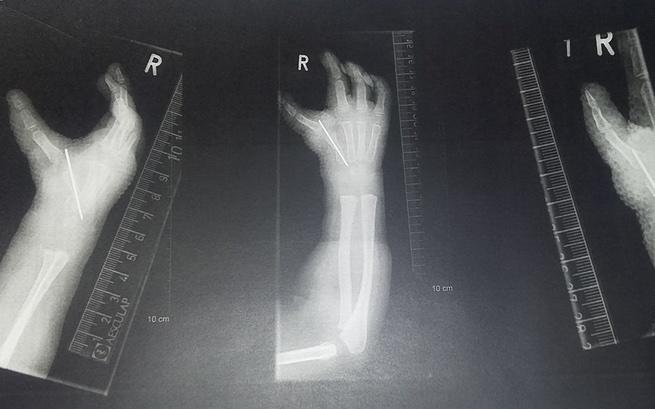

Nieprawidłowa motoryka rąk i wyraźnie krótsza kość promieniowa coraz bardziej wpływają na postawę ciała. Ból jest coraz większy. Musieliśmy szybko podjąć decyzję o rozpoczęciu rehabilitacji. Córeczka jest zdezorientowana, a w naszym życiu coraz częściej pojawia się lęk. Staram się przed nią ukrywać moje emocje, ale Nadia czuje, że coś jest nie tak. Widzi swoje ograniczenia i coraz boleśniej zdaje sobie z nich sprawę.

Znalezienie pełnej diagnozy było dla nas priorytetem. Mój mąż zajął się tym od razu, jeszcze zanim ja i Nadia wróciłyśmy do domu. Musieliśmy wiedzieć, jakie mogą być konsekwencje… Co się dzieje z moim dzieckiem?! Miałam ochotę krzyczeć… Okazało się, że choroba sięga znacznie dalej. Ucierpiały nie tylko ręce, chore było także malutkie serduszko. Diagnoza to zespół wad wrodzonych Holt i Oram oraz wada serca ASD II. Jedna część leczenia już za nami, teraz przed nami poważne wyzwanie…

Może wydaje ci się, że brak kciuków to nic takiego? Że takie wady zwyczajnie się zdarzają? Po wspólnym powrocie do domu mój mąż spróbował funkcjonować tak przez kilka godzin… Wniosek był jeden, tak nie da się żyć! To jak skazanie na niepełnosprawność…

Wiem z doświadczenia, że ludzie patrzą na nas jak na dziwny przypadek… Bo przecież mamy wszystko, ale od życia chcemy więcej. Mamy w sobie dobro, pozytywne emocje i uśmiech dla każdego, ale to za mało. Bo do uzbierania środków, które zapewnią Nadii normalne, szczęśliwe życie potrzebujemy całej armii dobrych serc. Dołączcie proszę do nas! Nadia rośnie, a nieprawidłowe ułożenie kości rąk prowadzi do wad kręgosłupa, które mogą doprowadzić do kolejnych poważnych schorzeń… Jesteśmy zrozpaczeni, bo szukaliśmy pomocy już wszędzie!